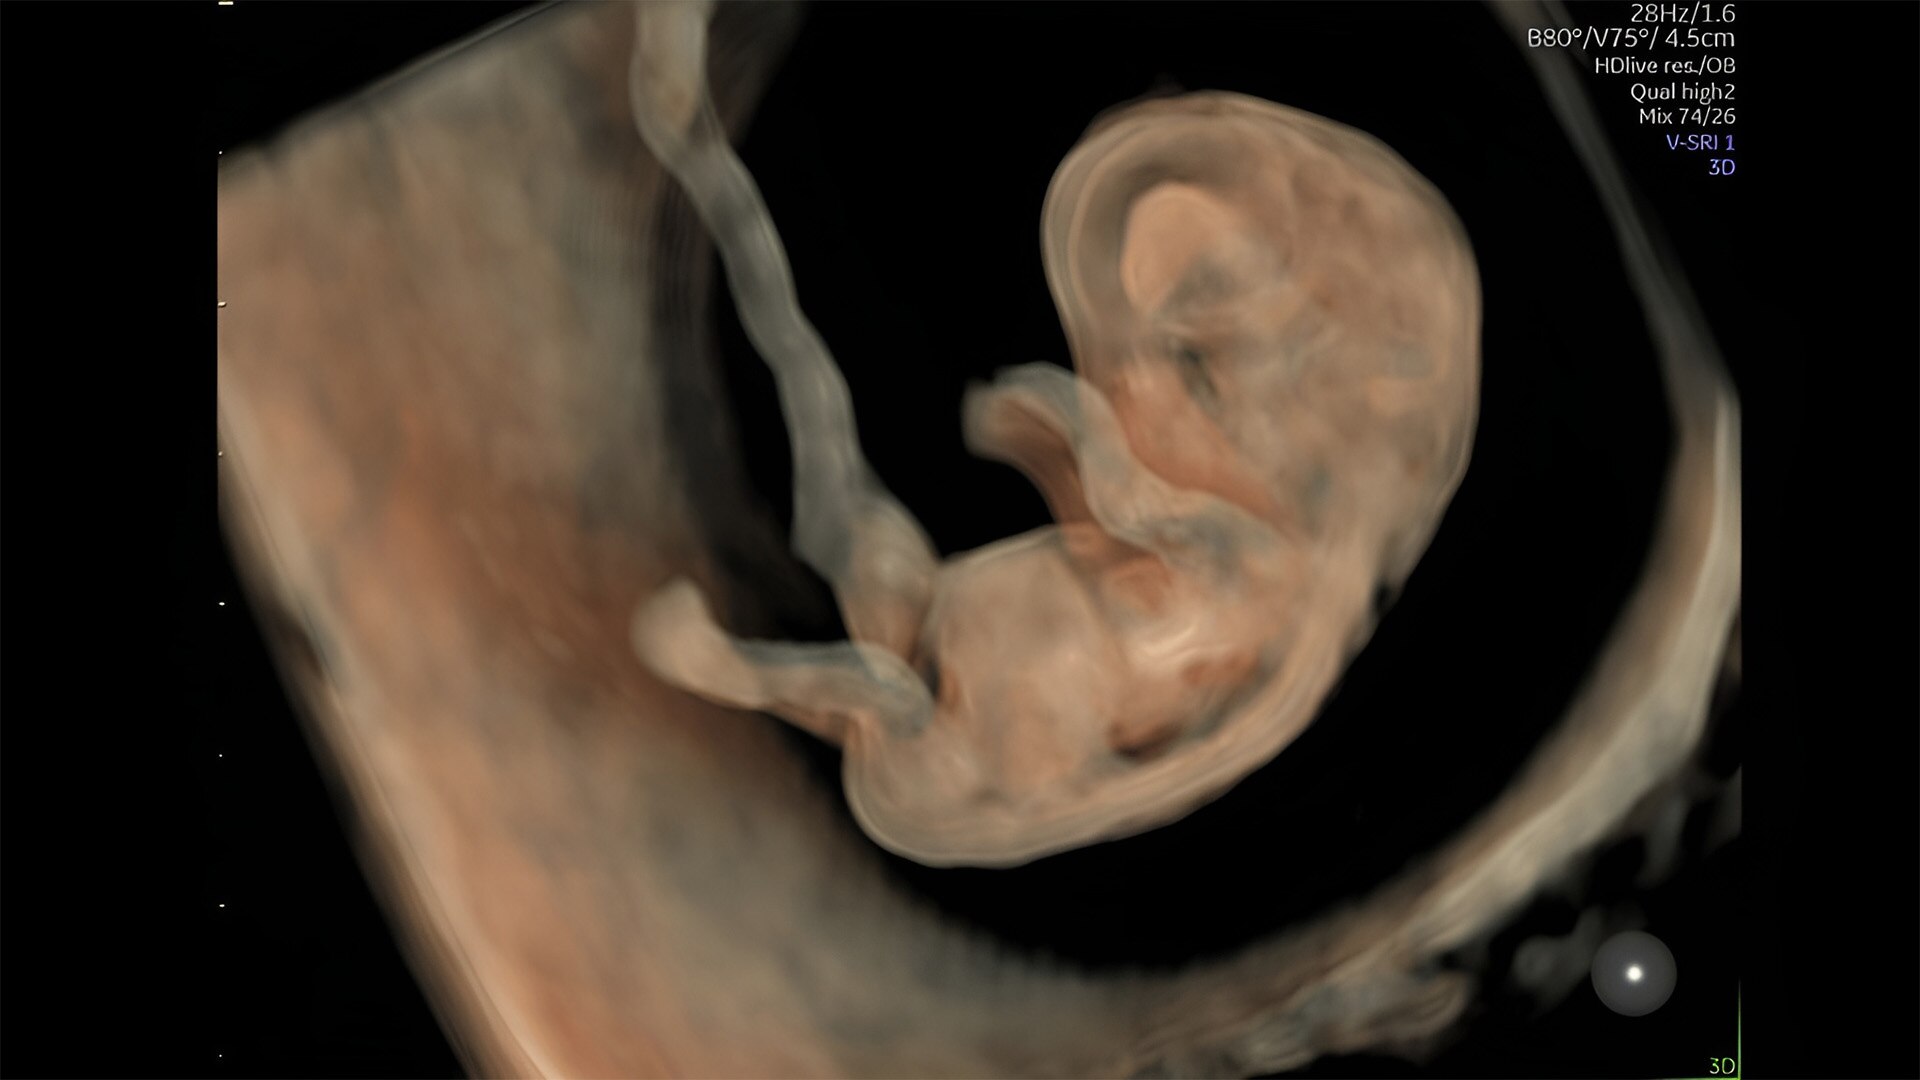

Complex cases come with enough uncertainty. That's why the Voluson Expert 22 is specifically designed for in-depth assessment of complicated anatomy — with pioneering first trimester, fetal cardiac, gynecological, and other pivotal technologies that focus on early detection and intervention.

First trimester exams

Perform detailed exams with high-resolution for early insights to fetal health